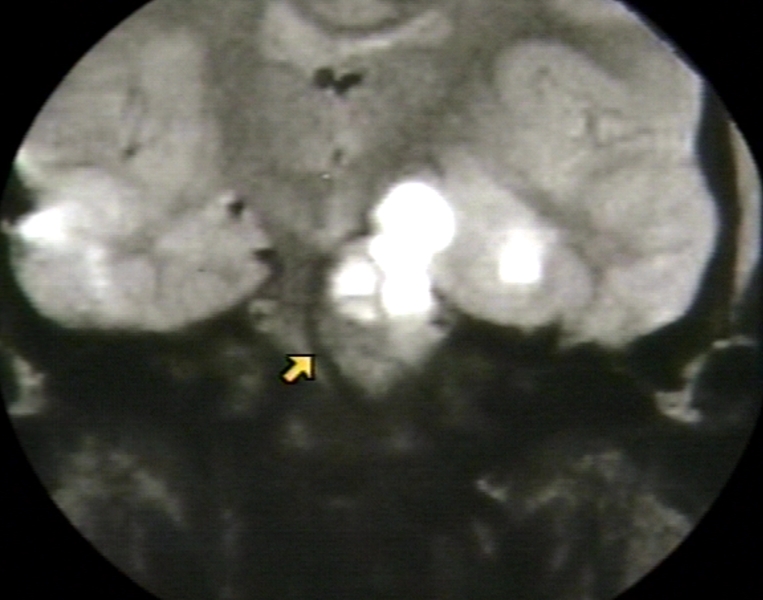

RADIOLOGY: NERVOUS: BRAIN: CRANIOPHARYNGIOMA, -NOTE BASILAR ARTERY DISPLACEMENT - WITH ARROWS (MRI)